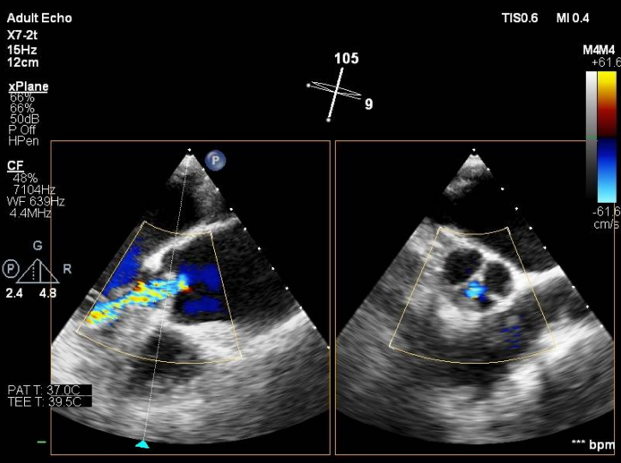

食道超声释放前

食道超声释放后

瓣膜释放后,食道超声及造影均提示瓣膜无残余反流。